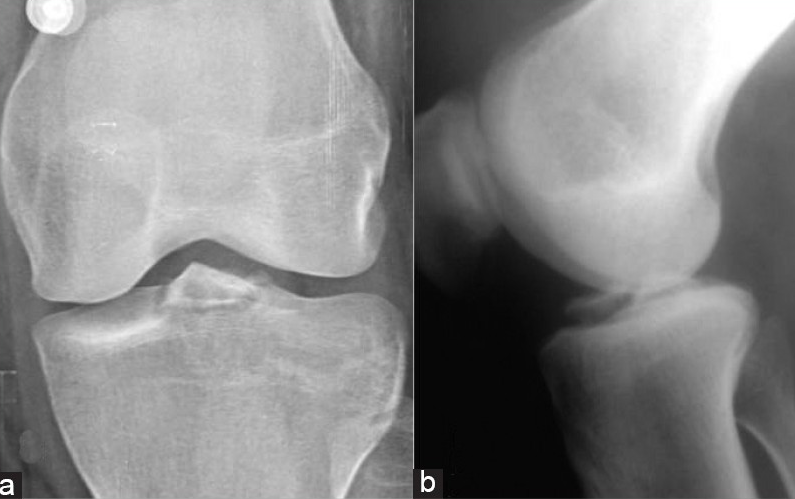

Pas. med fall på lett flektert kne. Bruker anabole steroider. Manglende ekstensjonsevne i kneet.

Quadricepsseneruptur. Må teste for ekstensjonsevne. partielle skader med intakt ekstensjonsevne forekommer.

Rtg kne front og side.

Skal alltid opereres.

Oppfølging: belastning på strakt ben, men ikke vektbelaste i særlig grad ved fleksjon de to første månedene. Ortose med gradvis økende leddutslag benyttes iblant.